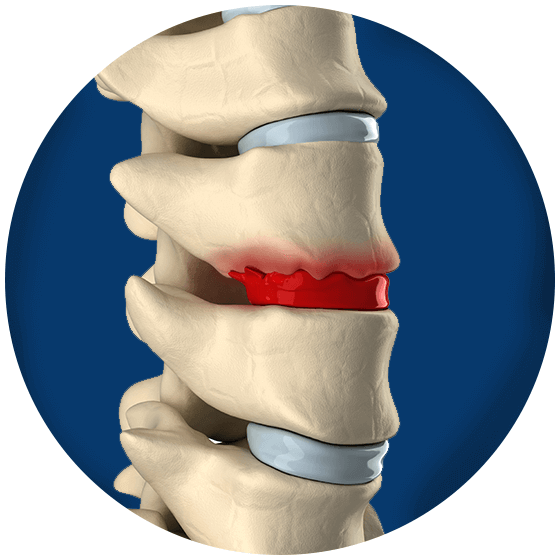

Disc In Neck: Bulging Disc In Neck With Bone Spurs

Bulging Disc | Bulging disc, Spondylolisthesis, Cervical

Dissecting Spinal Degeneration in the Neck (Neck Pain Support Blog)